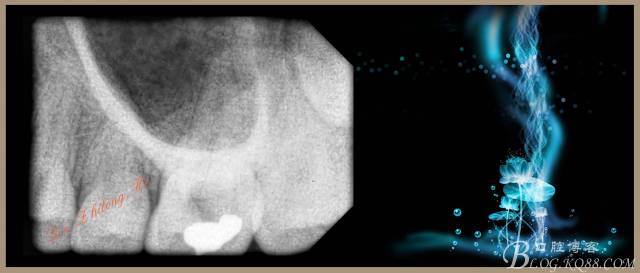

檢查:#26PO可見大面積黑色充填物,腭側(cè)充填物脫落少許,缺損深及髓腔,探(+++),叩(-),冷試驗敏感。X-ray示PO充填物近髓腔,根尖周無明顯異常。

4、試主尖,側(cè)壓充填法根充,拍根充片,聚羧酸鋅暫封。